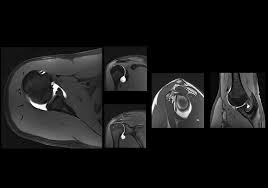

ام آر آرتروگرافی (MR Arthrography) چیست؟

ام آر آرتروگرافی (MR Arthrography)، که گاهی به اختصار ام آر آرترو (MR Arthro) نامیده می شود، یک روش تصویربرداری پیشرفته...